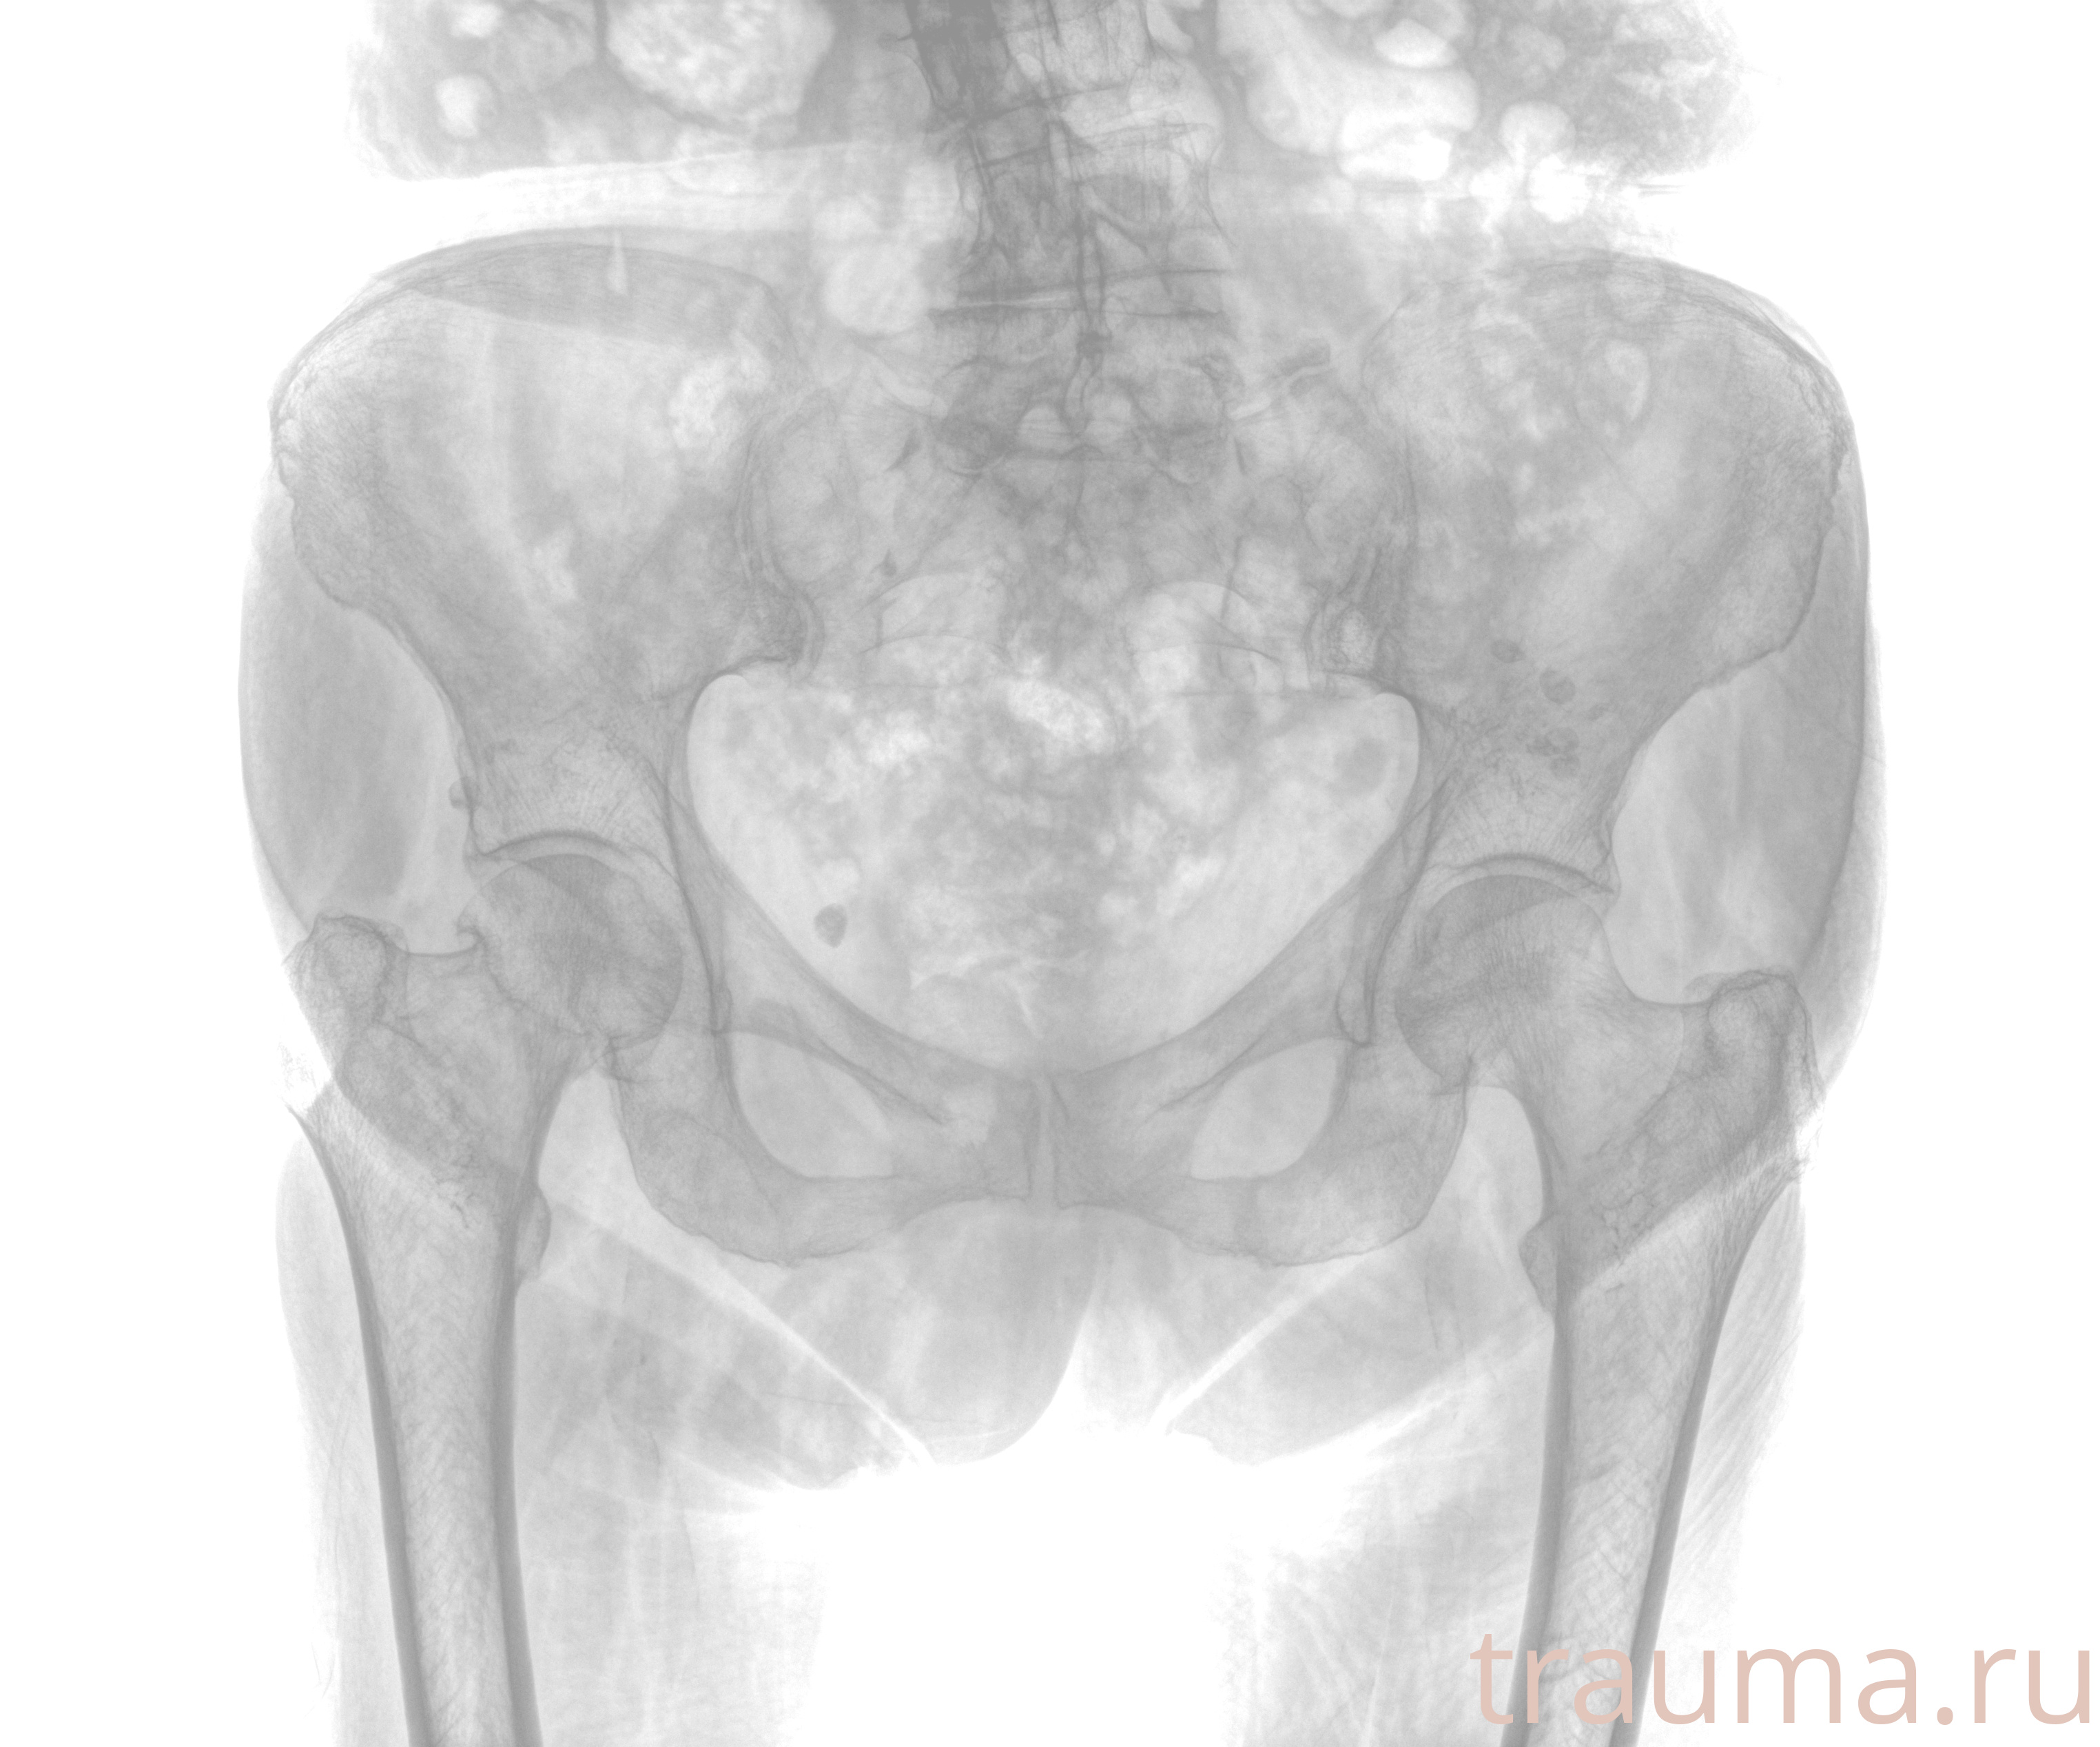

Рентген на дому: по вашему адресу приезжает врач-рентгенолог, травматолог-ортопед с мобильным рентгеновским аппаратом, проводит диагностику травмы или заболевания, делает необходимые рентгенограммы, дает рекомендации по дальнейшему лечению. Получить качественные снимки в домашних условиях возможно благодаря уникальной методике, разработанной МосРентген Центром для института  Склифосовского